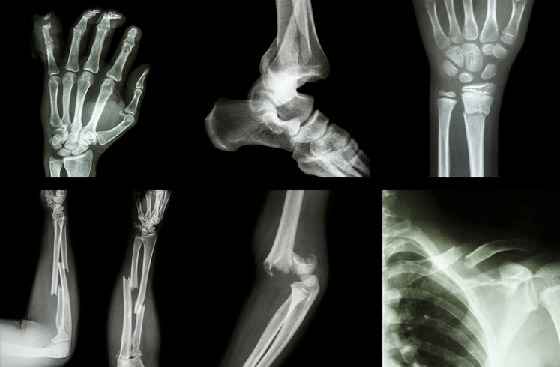

إليكم 5 معتقدات خاطئة حول كسور العظام

الكسور، على عكس ما يعتقد البعض، قد لا تسبب آلاما مبرحة في بعض الأحيان، وقد لا تعوقك عن الحركة. وفي هذا المقال، تفند كلوديا هاموند بعض المعتقدات الخاطئة حول كسور العظام.